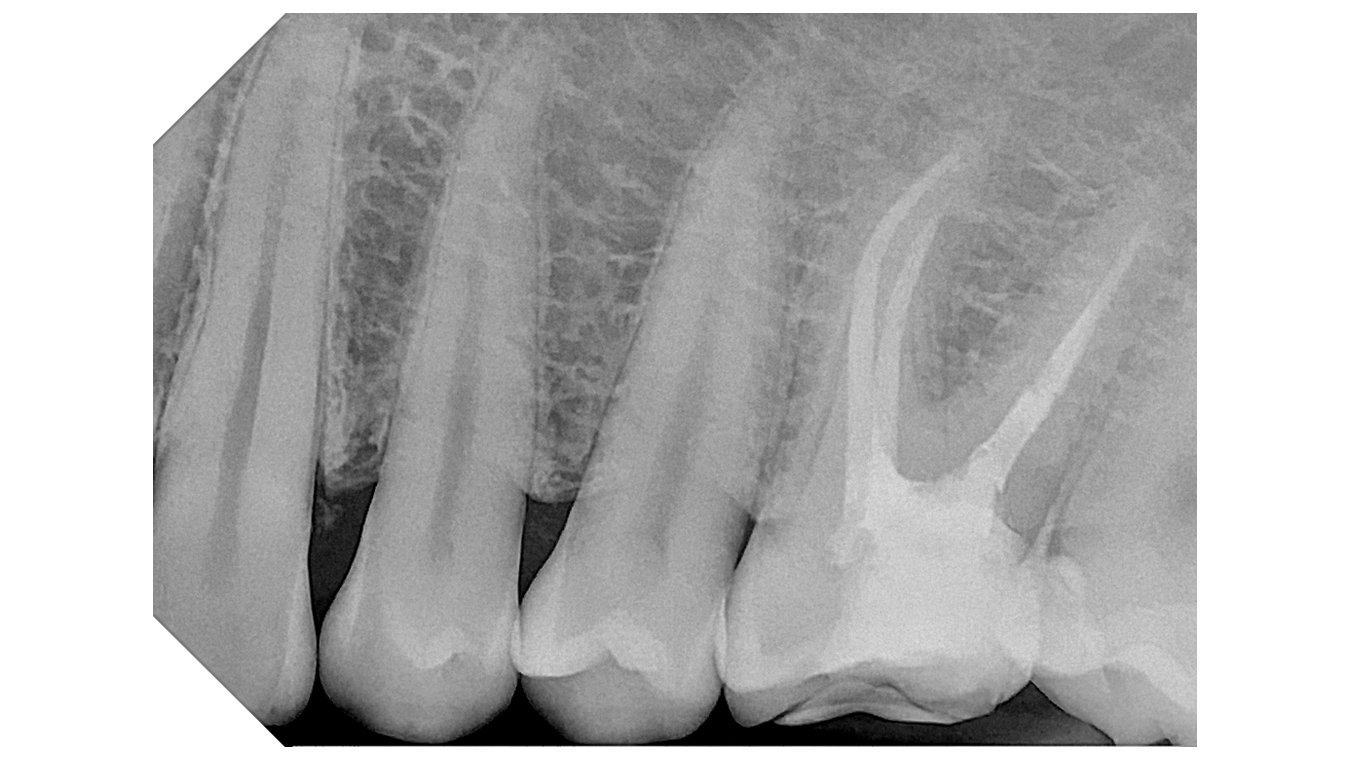

Integrated with the supplied software, the system offers advanced analysis tools and a selection of specific filters to improve image readability in line with clinical requirements:

Default:

High Contrast

High Details

Soft Tissue Preserving

Caries Revealing